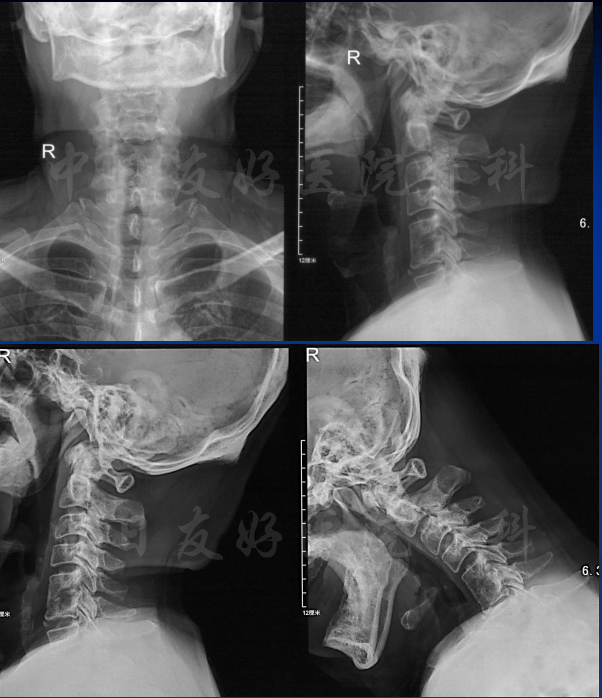

影像学检查

颈椎X片

颈椎MRI